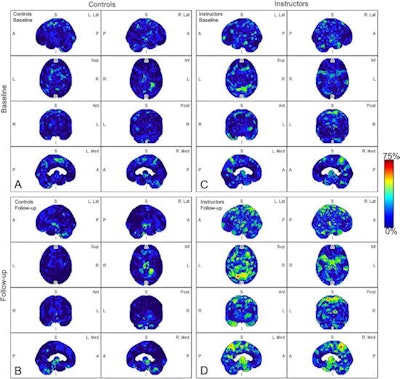

Parametric maps of amyloid deposition in healthy control participants (A and B) and blast-exposed military instructors (C and D) at baseline (A and C) and follow-up (B and D). The blue-to-red scale indicates the frequency of statistically abnormal amyloid uptake in a particular brain voxel. Whereas no abnormal amyloid uptake was identified at baseline or follow-up in healthy control participants (A, B), amyloid deposition occurred most frequently in blast-exposed participants in the superior parietal lobules, precuneus, cingulum, paracentral lobules, and anterior temporal and occipital lobes (D). Image and caption courtesy of Radiology.In a comparison between the groups, blast-exposed participants showed significantly increased amyloid deposition in four brain regions known to be abnormal in Alzheimer's disease: the inferomedial frontal lobe, precuneus, anterior cingulum, and superior parietal lobule. Conversely, no amyloid deposits were observed in the control participants.